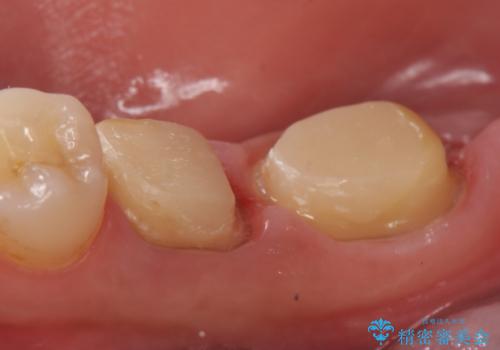

- 奥歯が欠けてしまったので診て欲しいといらっしゃった方の症例です。

再根管治療終了後、オールセラミッククラウンによる補綴を行いました。

今回用いたオールセラミッククラウンはジルコニアフレームという白い素材の上にセラミックを盛っているため、審美性が非常に高いのが特徴です。

また、ジルコニアは人工ダイヤモンドの材料にも使われているほど高い強度を持っており、そのためオールセラミッククラウンは審美性だけでなく、奥歯やブリッジの補綴も可能とするクラウンです。